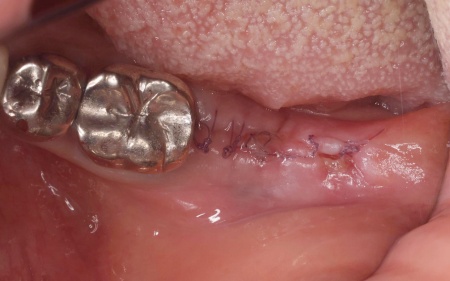

治療後

インプラント体と骨の結合を確認しました。